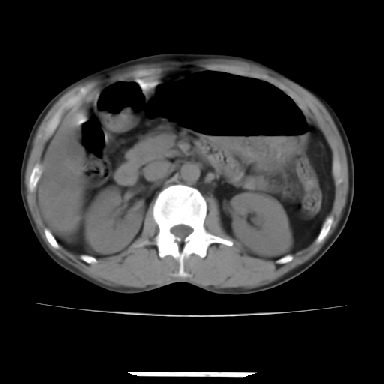

标题: CT7372:脂肪肝?外伤?

m 45 车祸,硬膜下血肿

窗宽太宽,调低点就好了,应该是不均质脂肪肝表现,请结合临床,单纯肝挫伤  其内无出血灶很少见,必要时做mri检查

窗宽太大,对比度太差了。局限性脂肪肝也有可能,但是亦不排除外伤性改变,增强扫描应该也还可以鉴别的。

肝内未见出血灶,但不能除外外伤性肝损伤,所示层面应考虑弥漫性脂肪肝.请结合临床必要时做mir检查

考虑不均匀性脂肪肝,建议增强扫描进一步检查除外合并其它病变。

肋骨无骨折,腹腔未见游离液体,所以不均匀脂肪肝首先考虑,但如果病人情况允许还是做个增强检查放心

考虑不均匀性脂肪肝,肝包膜下光整,肋骨无异常,无腹水征,不支持肝挫伤。